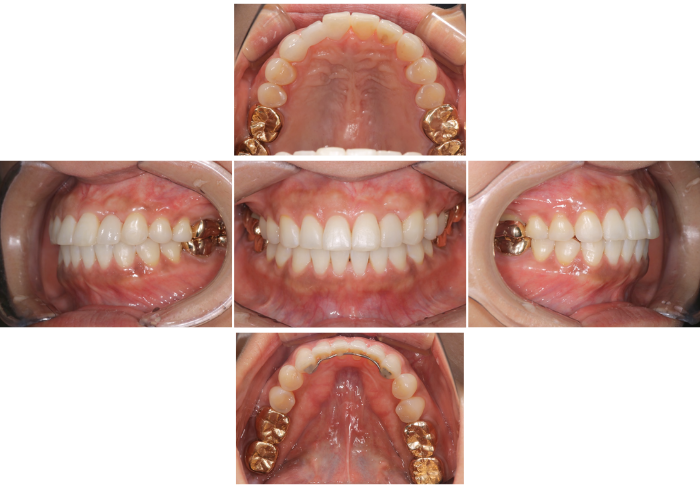

Before

After

患者の症状:他院で矯正したが前歯の並びが気になるのと前歯がオープンバイトとなっている

治療方法 :左上2がアンキローシスにより骨と固定されており、歯と歯肉のポジションの改善のため抜歯を選択、TADを用いて臼歯の圧下を行いオープンバイトの改善

治療結果 :歯並びの改善とともに審美はもちろん機能的にも改善することができた